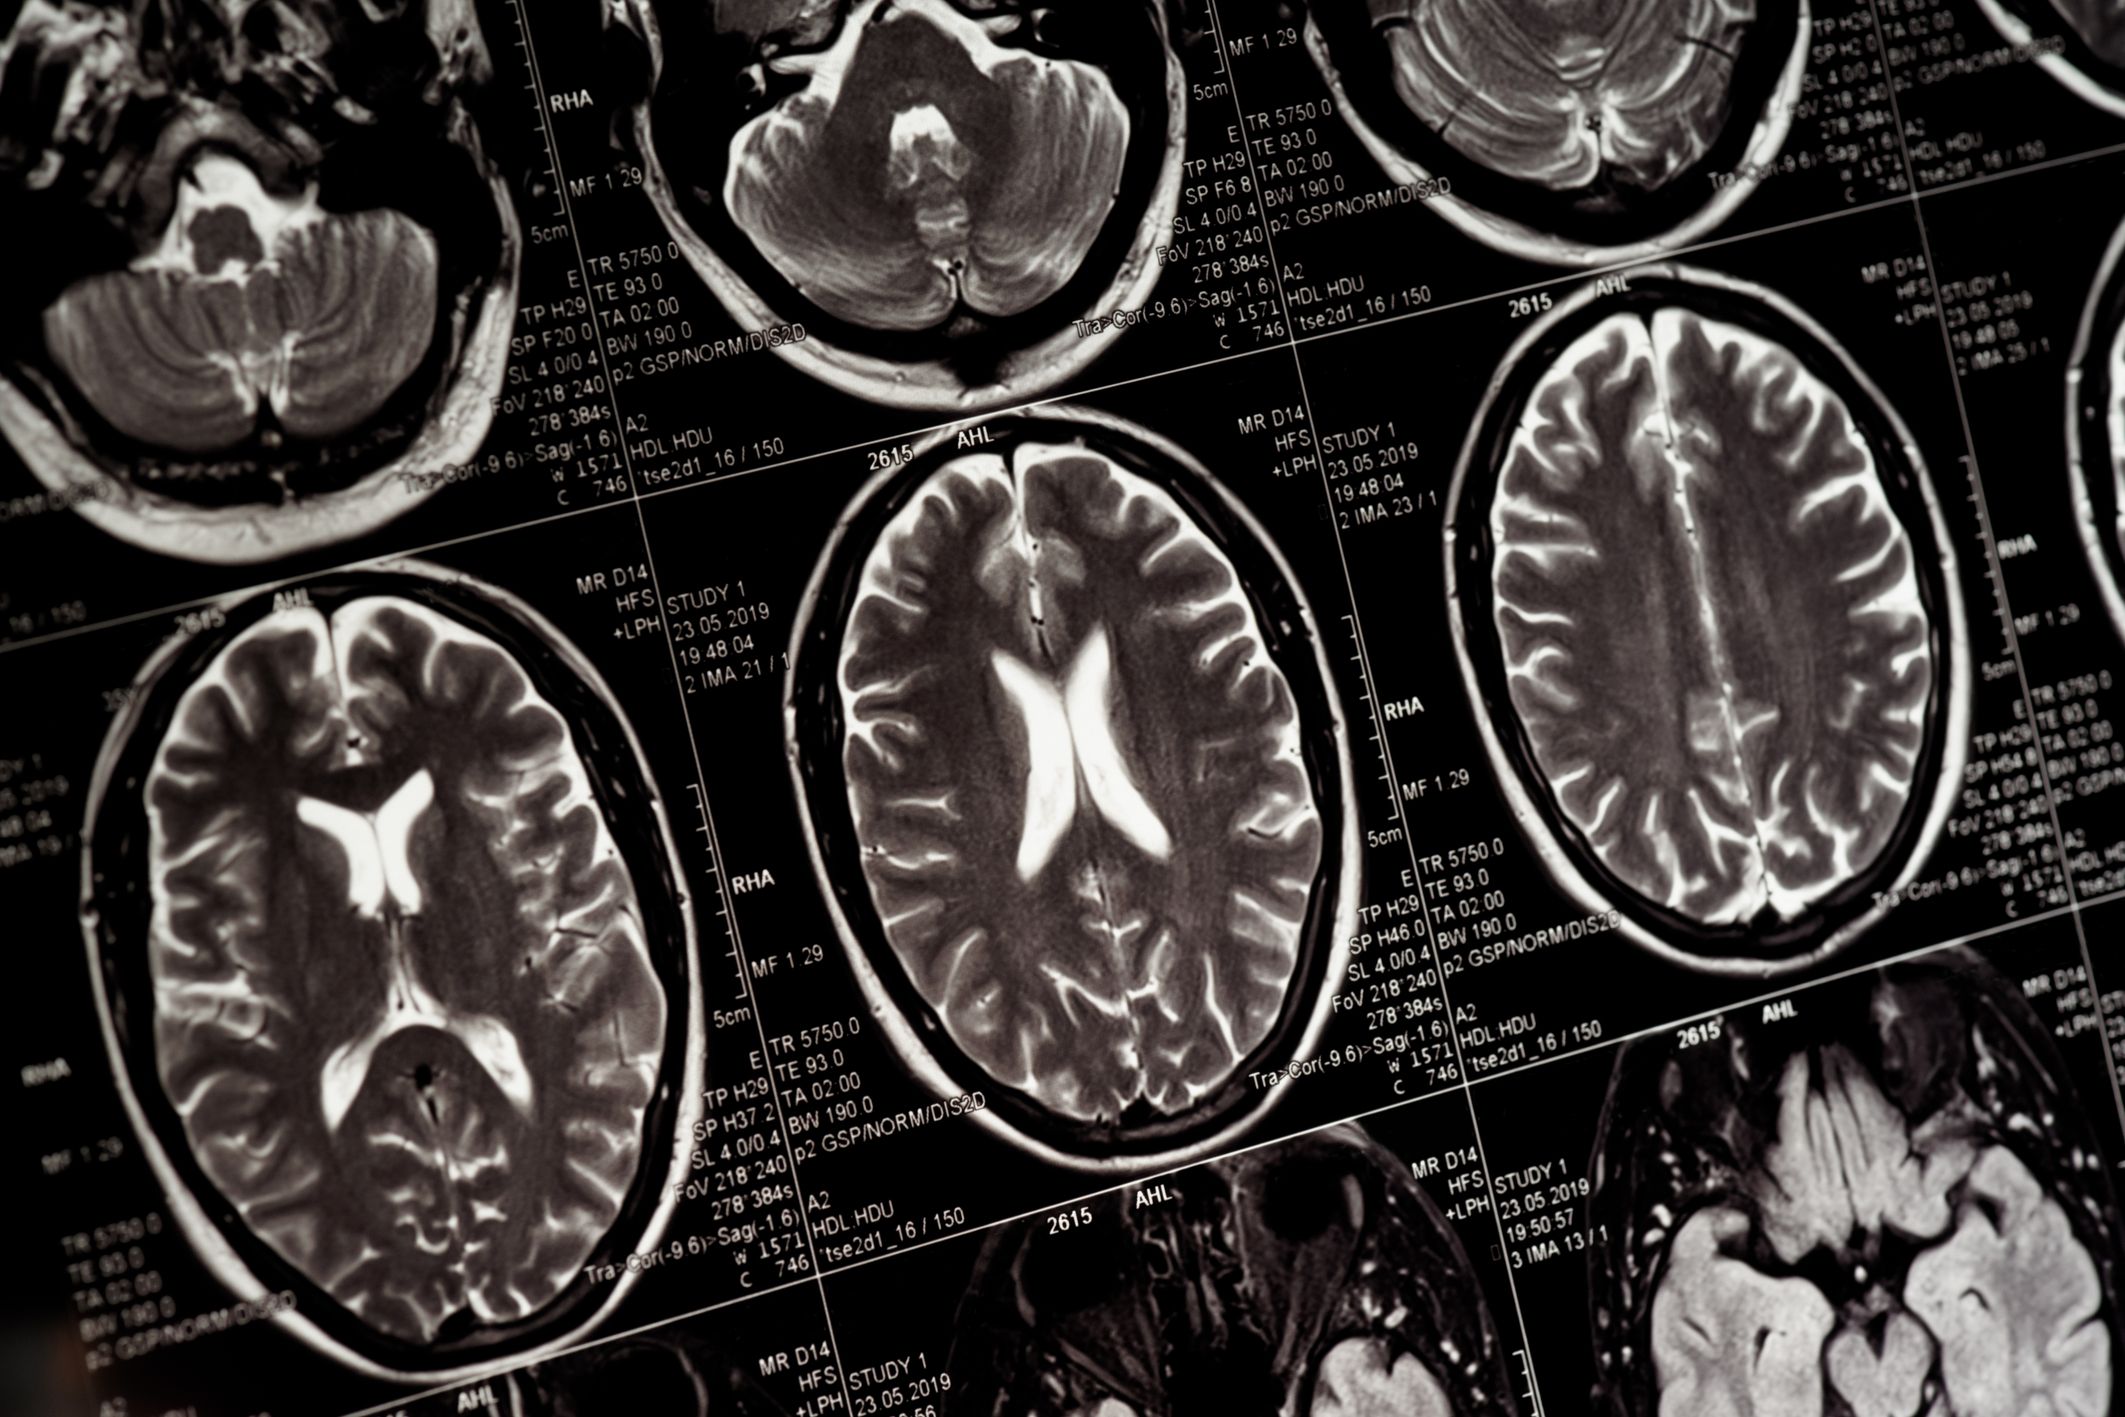

สิ่งที่มาคู่กับเรื่องผีก็คือความกลัว เป็นสิ่งที่จะเกิดขึ้นทุกครั้งในยามที่เราได้ฟังเรื่องผี โดยในทางวิทยาศาสตร์แล้ว ความกลัวเกิดขึ้นอย่างรวดเร็วในสมอง เมื่อประสาทของเราสัมผัสรับรู้ถึงภัยคุกคามใด ๆ ข้อมูลนั้นจะถูกส่งตรงไปยังอะมิกดาลา ส่วนเล็ก ๆ ในสมองสมองที่มีส่วนสำคัญในการควบคุมอารมณ์ ซึ่งเปรียบเสมือนสัญญาณเตือนภัยหลักของสมอง อะมิกดาลาจะทำการประเมินสถานการณ์ทันทีว่าเป็นอันตรายหรือไม่

หลังจากประเมินสถานการณ์แล้วจึงสั่งการให้ร่างกายเตรียมพร้อมสำหรับปฏิกิริยา สู้หรือหนี (Fight-or-Flight) คำสั่งนี้จะกระตุ้นการหลั่งฮอร์โมนอะดรีนาลีน และฮอร์โมนคอร์ติซอล ฮอร์โมนที่ผลิตในต่อมหมวกไตเพื่อตอบสนองต่อความเครียด ความกลัว หรือความตื่นเต้น ทำให้เกิดการเปลี่ยนแปลงทางกายภาพ เช่น อัตราการเต้นของหัวใจเพิ่มขึ้น การหายใจถี่ขึ้น รูม่านตาขยาย และกล้ามเนื้อเกร็งตัว เพื่อเตรียมร่างกายให้พร้อมรับมือหรือหลบหนี

หลังจากนั้นไม่นาน ข้อมูลก็จะถูกส่งต่อไปยังสมองส่วนหน้าเพื่อทำการคิดวิเคราะห์ ตรวจสอบซ้ำข้อมูลที่ถูกส่งมา หากสมองส่วนนี้ประเมินแล้วว่าภัยคุกคามนั้นไม่เป็นอันตรายจริง ๆ ก็จะส่งสัญญาณกลับไปยับยั้งการทำงานของอะมิกดาลา ทำให้ปฏิกิริยาทางกายสงบลงและเกิดความรู้สึกโล่งใจตามมา จากขั้นตอนดังกล่าวจะเห็นได้ว่าความกลัวคือแรงกระตุ้นที่สำคัญที่สุด ให้สมองเกิดการการทำงานจนนำไปสู่การเกิดปฏิกิริยาของร่างกาย ถ้าไม่มีความกลัวก็จะไม่มีสิ่งเหล่านี้เกิดขึ้น

จากหลักการทางวิทยาศาสตร์และมุมมองทางจิตวิทยาน่าจะพอทำให้เราทราบได้ว่า เมื่อเราฟังเรื่องผี ความกลัวจะถูกส่งไปยังอะมิกดาลาอย่างรวดเร็ว เพื่อประเมินภัยคุกคามจนเกิดความตื่นตัว หัวใจเต้นเร็ว เหงื่อออก ขนลุก และเมื่อข้อมูลถูกส่งไปประมวลผลในสมองส่วนหน้าก็จะพบว่าความกลัวที่เกิดขึ้นนั้นมาจากเรื่องเล่า ไม่ได้มีความอันตราย และเมื่อฟังเรื่องผีจบลงหรือผ่านพ้นช่วงที่น่ากลัวที่สุดไปได้ สัญญาณความกลัวของอะมิกดาลาจะถูกยับยั้ง พร้อมกันนั้นสมองก็จะทำการหลั่งโดปามีนออกมา ทำให้รู้สึกดี และพึงพอใจ

จะเห็นได้ว่าความกลัวที่ปลอดภัยสามารถสร้างประสบการณ์ที่ดีต่อความรู้สึกให้กับมนุษย์ได้ กระตุ้นปฏิกิริยาให้ผลลัพธ์เชิงบวก สร้างความสุขผ่านการหลั่งสารโดปามีนที่ทำให้เกิดความรู้สึกโล่งใจ เปลี่ยนจากสภาวะตื่นตัวสุดขีดไปสู่สภาวะผ่อนคลาย สบายใจ มีความสุข การฟังเรื่องผีจึงเป็นเหมือนการฝึกฝนระบบความกลัวของสมองในสภาพแวดล้อมที่ควบคุมได้ (ปลอดภัย) ทำให้ได้รับทั้งความตื่นเต้นทางกายภาพจากอะดรีนาลีน และความสุขทางจิตใจจากโดปามีน เป็นกลไลที่ทำให้เราอยากฟังเรื่องผีอีกครั้งนั่นเอง